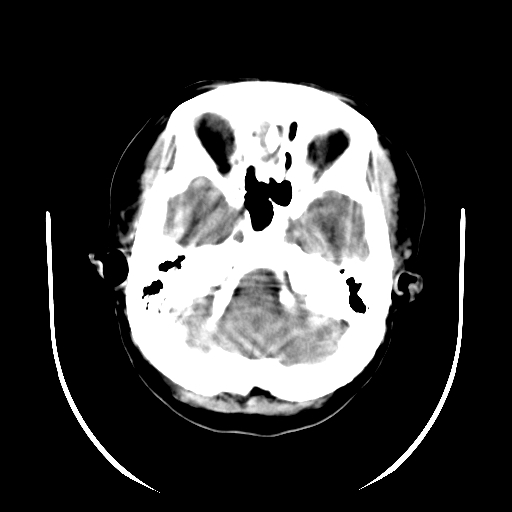

标题: CT19189:女,38岁,右侧肢体偏瘫、失语5天。 [打印本页]

女,38岁,右侧肢体偏瘫、失语5天,发病1小时曾在外院做头颅ct检查未见异常。

左侧基底节区、顶叶出血性脑梗塞,建议增强扫描或做cta检查,协助定性。

左颞外囊区高密度病灶,周边脑白质指状水肿,低密度区不累及皮质,考虑是左外囊出血并脑水肿 。

这是发病5天时的ct片吗?如果是,仍考虑为:左侧外囊脑出血。(发病3-7天血肿变淡模糊血肿向心性回缩,水肿渐明显)。

另外,出血性脑梗塞不除外。